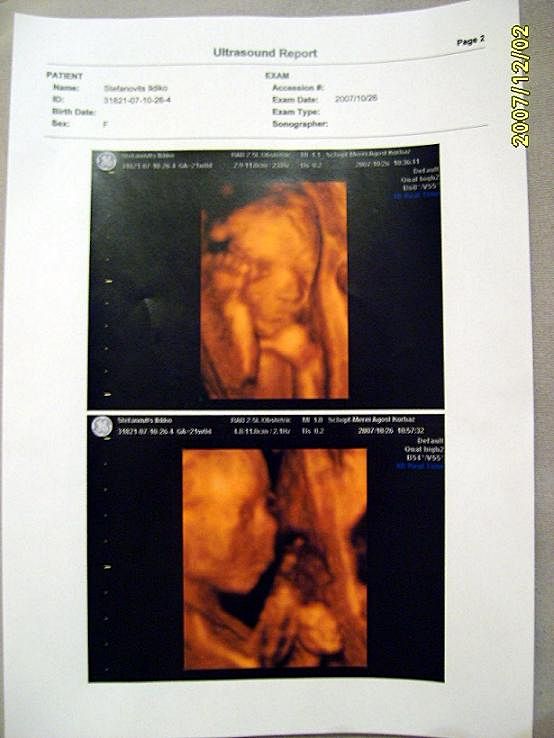

4D Ultrahang - 21+1 (07/10/26, Bp.)

Kinyomtatott képek 2